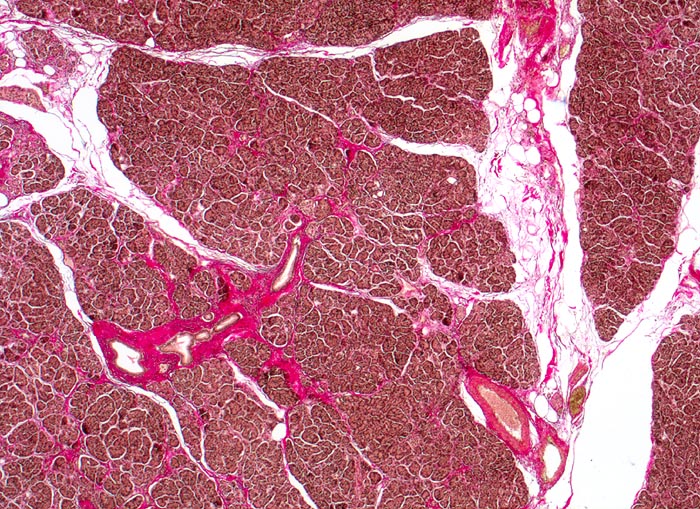

Normales exokrines Pankreas

In der Übersicht wird die Lobulierung des Pankreasparenchyms sichtbar. Zwischen den Läppchen verlaufen schmale Bindegewebssepten mit Ausführungsgängen und Gefässen.